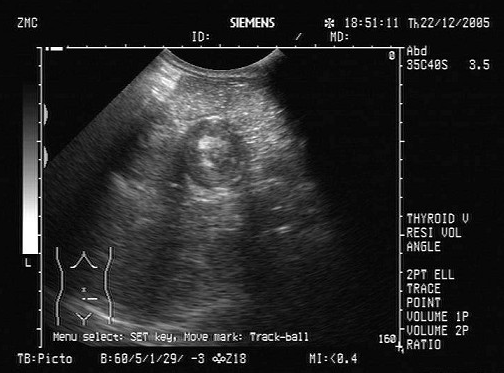

某患者自诉乳腺可触及一包块,光滑可移动,超声图像如图,诊断为()

A.纤维瘤

B.囊肿

C.乳腺癌

D.小叶增生

E.乳腺导管扩张